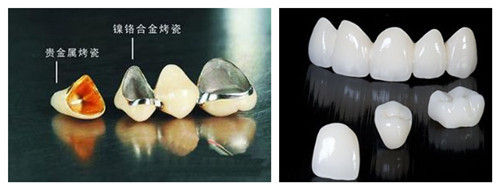

非贵金属烤瓷牙虽然价格低廉,但是与组织的相容性差,刺激性较大,可发生过敏现象及变色,因此不建议患者选用这种材料的烤瓷牙。

半贵金属烤瓷牙的代表是钛合金,主要成分是钛或者钯-银,钛合金烤瓷牙的价格介于非贵金属和贵金属之间,其生物相容性优于非贵金属,也比较耐久,可以避免牙龈出血及牙龈黑线的出现,而且经济、实用,适合大多数牙齿的修复,尤其适合后牙固定桥等固定修复。>>>更多详情,在线咨询<<<

贵金属烤瓷牙的代表就是金合金烤瓷牙。黄金在我国很早就用作补牙的材料了,它是较理想的修复材料之一,拥有钛合金的优点,且强度更高,无刺激,而且金与瓷的结合很牢固,与组织的相容性更好,在瓷牙与牙龈接触的地方不会发黑。

另外,瓷粉能在黄金的表面反映自身的颜色,使烤瓷牙更美观,能满足美容修复的要求。>>>更多详情,在线咨询<<<